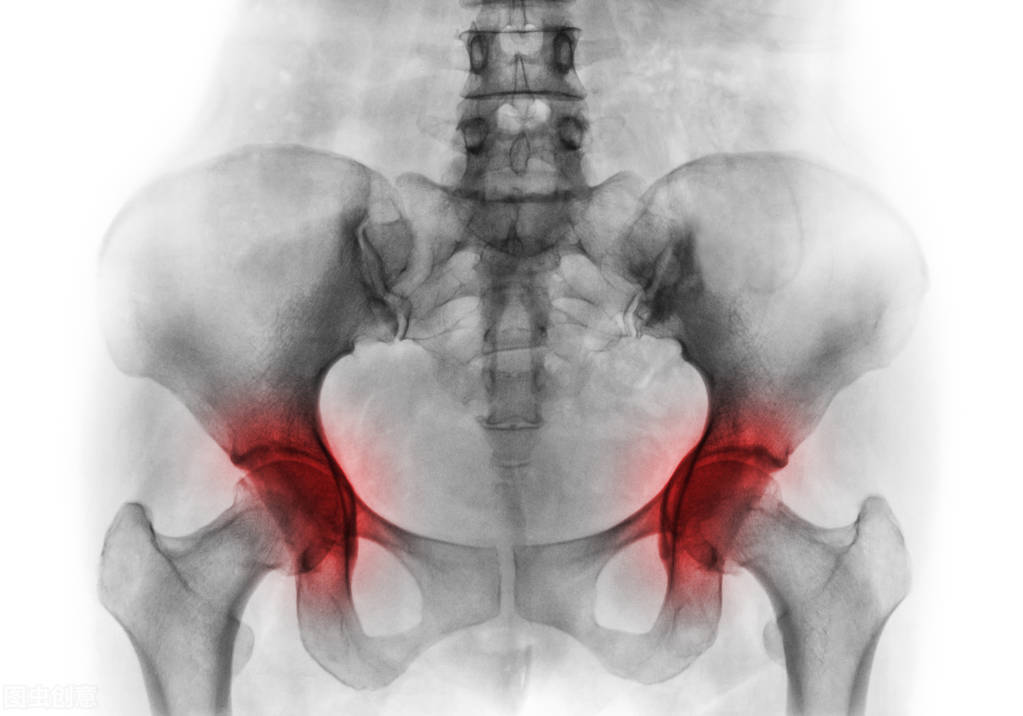

在临床病例中,大多数股骨头坏死患者早期无明显体征表现, 当向病患处施加重压时,受影响的关节才会出现疼痛感。

随着病程发展, 疼痛感会持续增强, 患者即使患肢不活动,也会感到疼痛, 并严重影响患肢的正常活动。

如果不及时就诊,病症发展至后期,由于 髋部血管持续受压的状况下,会导致骨关节炎和永久性活动障碍!